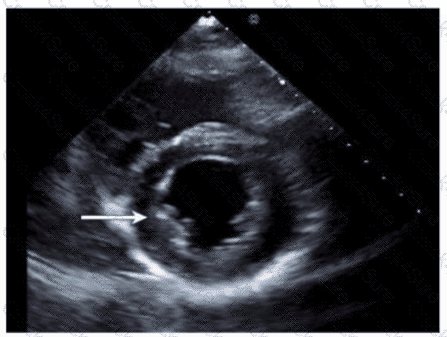

Which wall is indicated by the arrow on this image?

Which left ventricular regional wall segment is indicated by the arrow on this image?